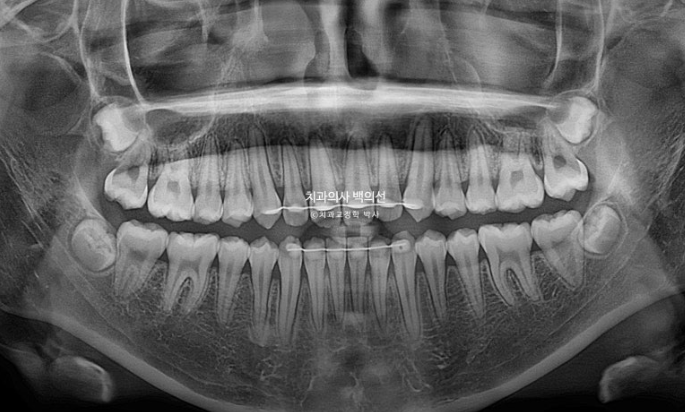

25.04

엑스레이상 치근흡수는 없고 치근평행도는 양호합니다.

총 치료기간은 1년 6개월입니다.

그 중 4개월은 악궁확장기간, 인비절라인 장치를 낀 기간은 1년 2개월이며 나머지는 인비절라인 장치 제작기간이었습니다.